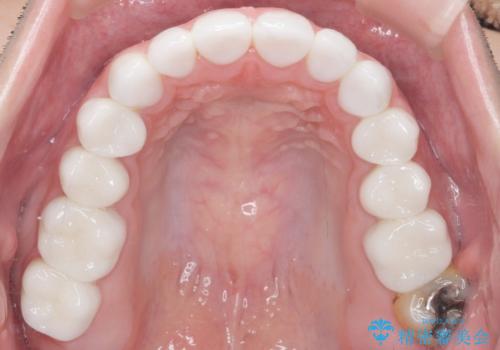

見た目と咬み合わせを改善するため、セラミッククラウンによる治療を行いました。

綺麗な仕上がりにご満足下さいました。

奥歯の咬み合わせも良くなったと喜んで頂けました。

患者様の理想とする韓流アイドルの写真を技工士さんに送り、最終的なクラウンの形や色をできるだけ理想に近づけられるよう努めました。

クラウンの種類:オールセラミッククラウン スタンダード